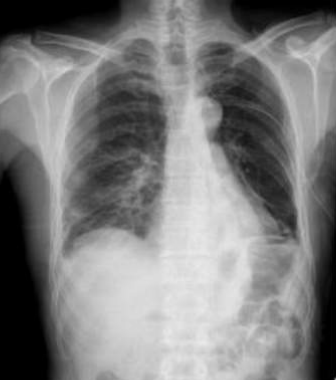

![]() |

RĂ©gression du pneumothorax droit./Drain en place au niveau apical droit./OpacitĂ© en bande linĂ©aire au niveau du tiers infĂ©rieure de lâhĂ©michamp pulmonaire gauche./Scissurite droite./Silhouette cardiaque dâaspect normal./Absence dâanomalie du gril costal./ | StabilitĂ© du pneumothorax droit./Drain apical droit en place et fonctionnel./Bande opacifiante au niveau du tiers moyen de lâhĂ©michamp pulmonaire gauche./LĂ©gĂšre scissurite droite./ | Diminution du Pneumothorax gauche./Drain thoracique positionnĂ© Ă l'apex gauche./OpacitĂ© linĂ©aire sur le tiers supĂ©rieur de l'hĂ©michamp pulmonaire droit./ | RĂ©gression marquĂ©e du pneumothorax droit./Disposition dâun drain au niveau apical gauche./OpacitĂ© linĂ©aire dans le tiers infĂ©rieur de lâhĂ©michamp pulmonaire gauche./NormalitĂ© du gril costal et des parties molles./ |